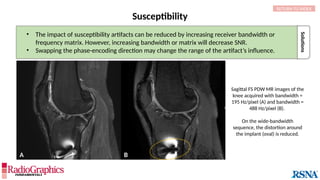

Susceptibility

Sagittal FS PDW MR images of the

knee acquired with bandwidth =

195 Hz/pixel (A) and bandwidth =

488 Hz/pixel (B).

On the wide-bandwidth

sequence, the distortion around

the implant (oval) is reduced.

Solutions

• The impact of susceptibility artifacts can be reduced by increasing receiver bandwidth or

frequency matrix. However, increasing bandwidth or matrix will decrease SNR.

• Swapping the phase-encoding direction may change the range of the artifact’s influence.